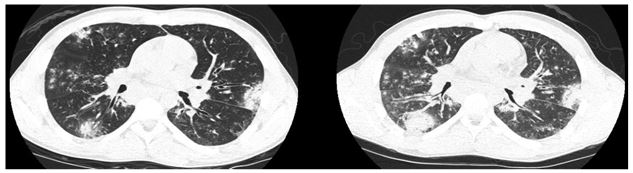

High resolution CT of the chest: (representative image shown; inspiratory (left) expiratory (right))